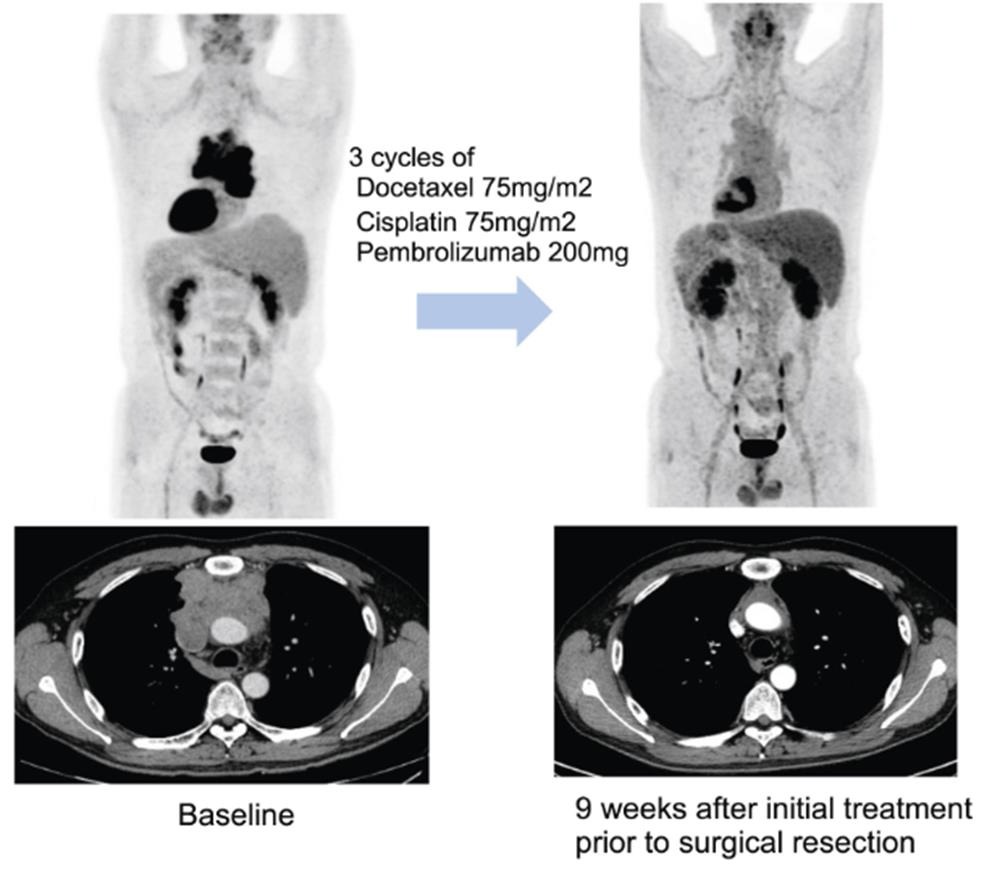

연구팀은 이들 환자에게 3주 간격으로 세 번에 걸쳐 기존 항암화학요법에 펨브롤리주맙을 병용 투여한 다음 수술 가능 여부를 평가했다.

연구팀은 추적관찰 기간 27.5개월(중앙값) 동안 전체 환자의 57.5%(23명)에서 수술 전 치료를 통해 종양의 크기가 유의미하게 감소하는 반응을 보였다고 했다.

치료 결과 병리 검사를 통해 암세포가 10% 이하로 감소한 지를 평가(MPR)했을 때 전체 환자의 32.5%(13명)가 도달한 것으로 나타났다.

당초 기대치 50%에는 미치지 못했지만, 수술 환자 놓고 보면 MPR 도달 비율은 46.4%로 증가해 펨브롤리주맙이 흉선상피종양 치료 선택지에 포함될 가능성에 파란불이 켜졌다.